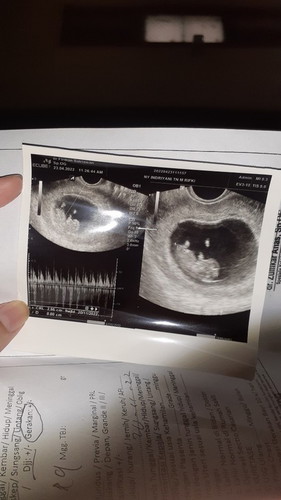

Bunda² aku mau curhat, karna lagi down, aku baru abis USG, tadinya USG biasa tapi janin ga kelihatan.. akhirnya di USG transvaginal janin baru nampak. menurut Hpht harusnya UK udh 12w4d. Tapi di USG 9w6d. Kata dokter janinnya telat berkembang dan tidak normal, karna jauh dari Hpht. Dokternya bikin aku down banget karna tutur katanya yg sama sekali gak support aku dan menyalahkan aku karna aku makan kurang gizi, jadi nutrisi janin tdk terpenuhi. Masya allah, emang saat ini aku lagi merasa mual dan muntag terus, tapi aku selalu berusaha utk makan semua, dan vit dan susu ga ketinggalan. Ada yg pengalamannya sama seperti saya kah bun, utk menguatkan hati aku, aku mau tau sharing dari bunda² yg lainnya ?? #bantusharing EDIT : nggak nyangka banget banyak yg support.. sehari post komen udah 50 lebih.. makasih banyak utk support, Do'a dan masukannya. berkat bunda² disini, perasaan saya sekarang jauh lebih baik, dan merasa tidak sendiri mengalami hal ini. Untuk semuanya yg sudah baik terima kasih, dan semoga bunda² semua diberi kesehatan sekeluarga.. semangat juga untuk semuanya, semoga semuanya bahagia selalu. aamiin..